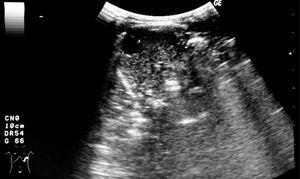

Se realizó ecografía abdominal durante la primera semana de vida, verificándose la presencia de quiste esplénico con 12 mm de diámetro y restantes órganos abdominales sin alteraciones (fig. 3). En controles ecográficos posteriores, se constató su progresiva disminución, hasta su desaparición a los 2 años de vida. Estuvo siempre asintomática y sin otras alteraciones clínicas.

Figura 3. Ecografía abdominal: quiste esplénico con 12 mm de diámetro.